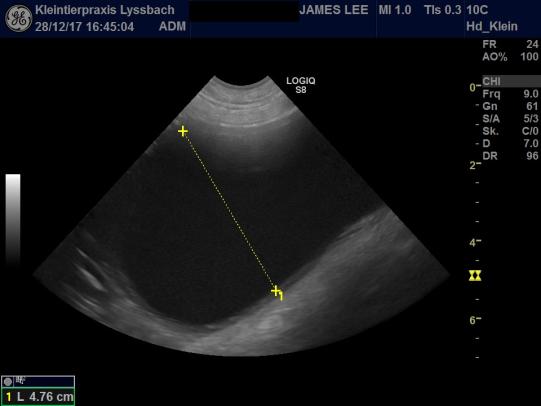

Ein halbes Jahr später kontrollieren wir die Blase des Rüden erneut mittels Ultraschall. Leider müssen wir feststellen, dass sich in der kurzen Zeit erneut ein Blasenstein von praktisch gleicher Grösse gebildet hat - und dies obwohl weiterhin ein Spezialfutter, welches eigentlich die Cystinstein-Bildung verhindern sollte, verabreicht worden war.